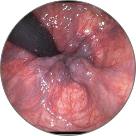

Hemoroidi su ozbiljna bolest koja pogađa jednu od dve osobe širom sveta. Bol, peckanje, svrbež i krvarenje početni su simptomi koje ni u kojem slučaju ne treba zanemariti. Kao rezultat ulaska krvi u venski pleksus rektuma, dolazi do upalnog stanja, nakon čega se na rektalnom tkivu stvaraju krvavi čvorovi.

• ŠTA HEMOROID MOŽE IZAZVATI?

Fekalna inkontinencija

Tromboza proširenih vena anusa sa lokalnom nekrozom tkiva

Venska zapušenja s patološki izmenjenim varikoznim venama